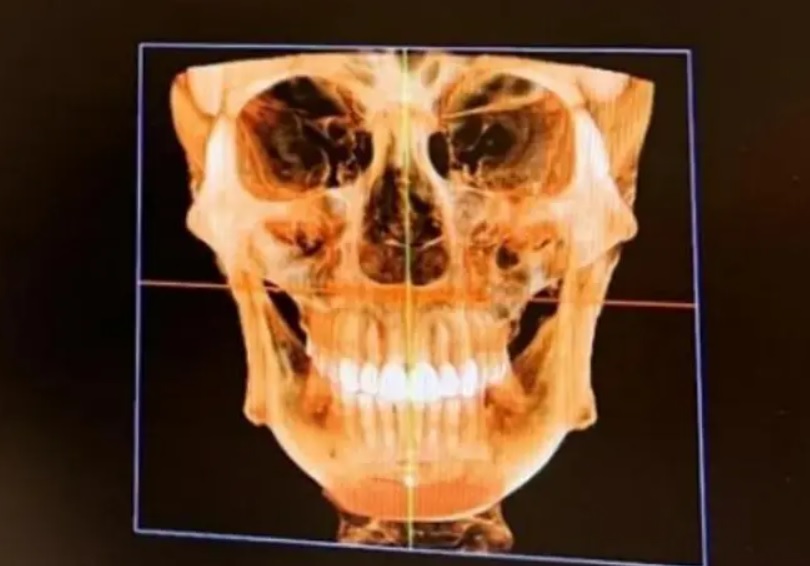

Controlul cu scanner din aeroprot ar fi semnalat prezența unui șurub chirurgical de 1 centimetru chiar sub buza de jos. Modelul crede că acel șurub a fost în corpul ei de când și-a pus o „proteză de bărbie”, în urmă cu opt ani.

„Am descoperit în mod neașteptat că am și unghii pe nas”, a mai exclamat modelul, șocată de ce a văzut că se află în corpul său.

Fang Qiyuan, în vârstă de 36 de ani, se autointitulează „fanatică a chirurgiei plastice”. Femeia are peste 19 operații plastice, între care două operații la frunte, cinci la pleoape, cinci la nas, două în bărbie și liposucție pentru repararea feței de cinci ori.